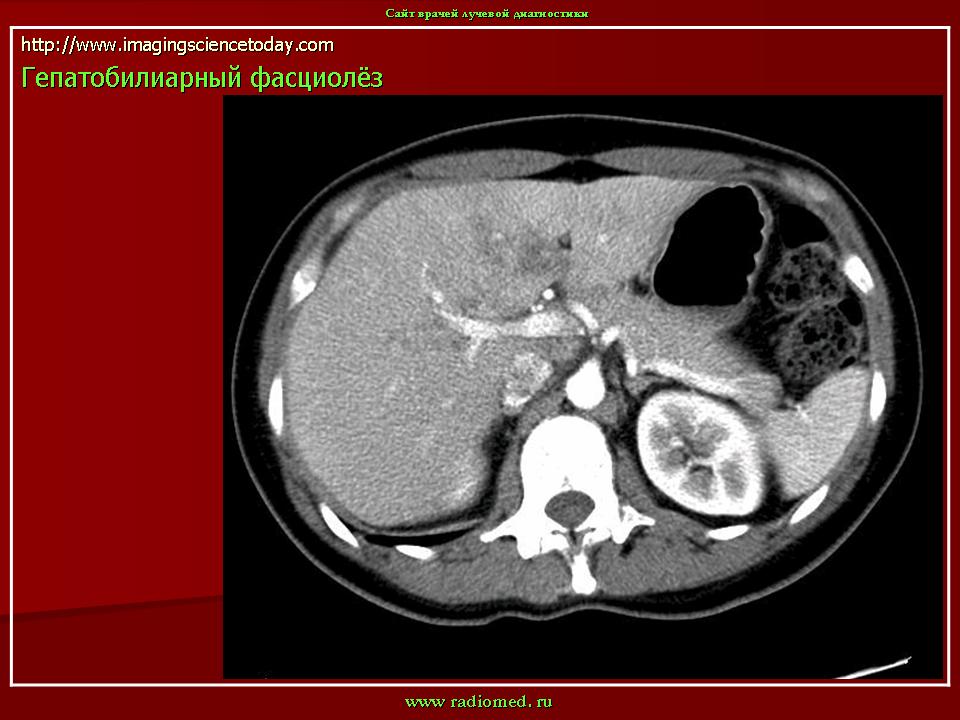

Фасциолёз. Пт, 09/03/2012 - 23:34 #1 Катенёв Валенти... Не на сайте Был на сайте: 7 лет 4 месяцев назад Зарегистрирован: 22.03.2008 - 22:15 Публикации: 54876 Клонорхоз.Приложения: